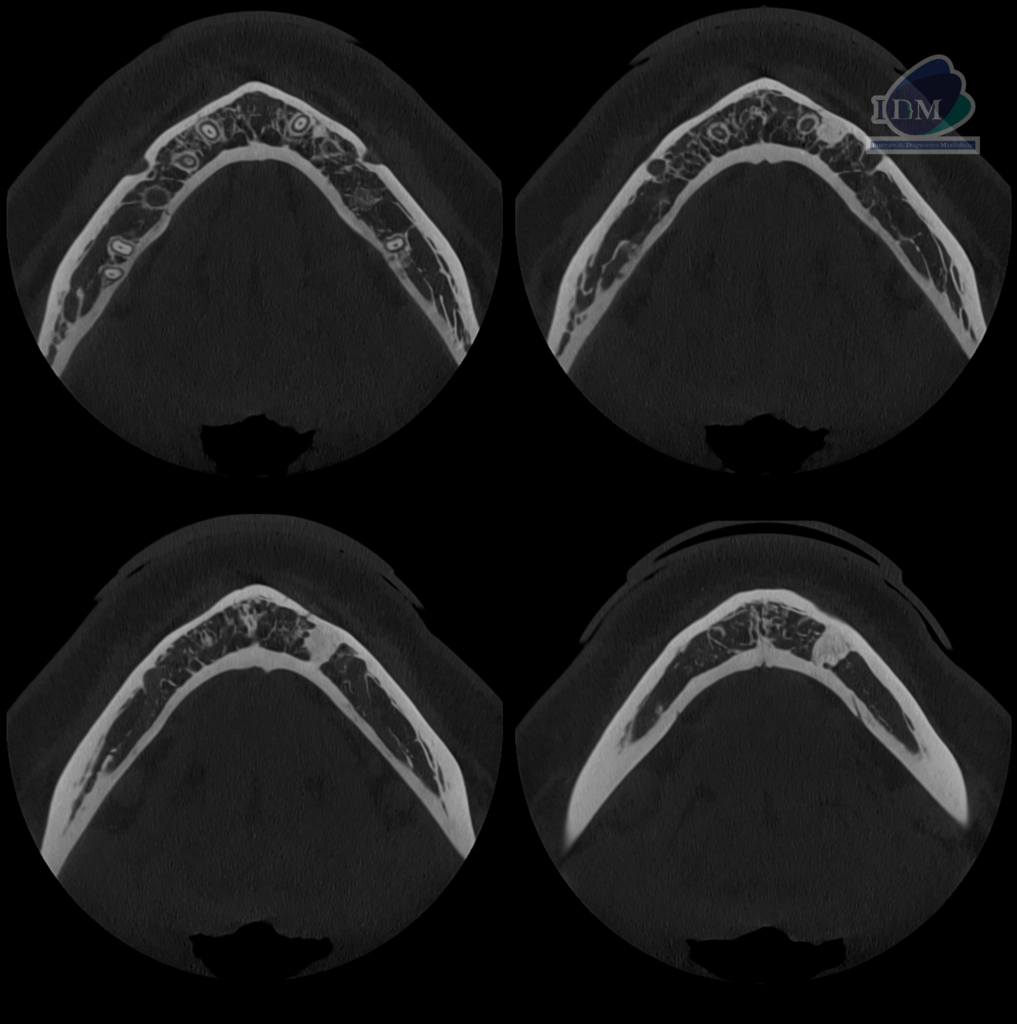

A la evaluación de la tomografía volumétrica (CBCT) en los cortes axiales (Figura 2) y transaxiales (Figura 3), se aprecia imagen hiperdensa intraosea, de limites definidos y forma irregular, que se extiende entre tabla ósea vestibular y lingual, sentido cefálico caudal desde nivel apical de pieza 33 hasta cortical superior del conducto dentario inferior, comprometiendo la cortical superior del conducto dentario inferior.

CORTES AXIALES